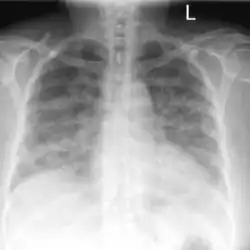

Acute pulmonary edema due to salt water aspiration syndrome

Recovery after 48 hours of supplemental oxygen

Chest x-rays of a 61-year-old female who developed salt water aspiration syndrome while swimming during a triathlon.[5]

Lung auscultation may reveal abnormal breath sounds such as rhonchi (snoring-like) or crackles (rattling), and chest imaging can show lung consolidations[4] and edema.[5] Decreased lung volumes, including a reduction of average 0.7 liters in forced expiratory volume in 1 second and vital capacity, is found on spirometry. Laboratory studies do not show specific abnormalities, but low oxygen levels in blood, slightly elevated white blood cell count and lactate dehydrogenase levels may be seen.[1]